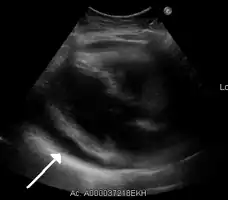

Ultrasounds showing a pericardial effusion in someone with pericarditis

The diagnosis of tamponade can be confirmed with trans-thoracic echocardiography (TTE), which should show a large pericardial effusion and diastolic collapse of the right ventricle and right atrium. Chest X-ray usually shows an enlarged cardiac silhouette ("water bottle" appearance) and clear lungs. Pulmonary congestion is typically not seen because equalization of diastolic pressures constrains the pulmonary capillary wedge pressure to the intra-pericardial pressure (and all other diastolic pressures).